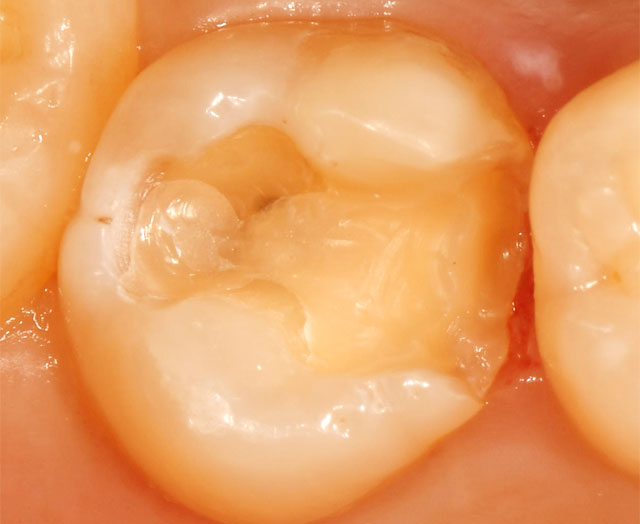

1.虫歯の範囲が狭い場合

• 虫歯の範囲が狭い場合は、虫歯を削った跡を処置し、コンポジットレジン(白い樹脂の詰め物)で埋めます。

• 埋めた後は、形や咬み合わせを調整し、研磨します。

この処置は、通常1回で終わります。

2.虫歯の範囲が広い場合

• 虫歯の範囲が広い場合は、型とりをして一度仮の詰め物をして終わります。

• 次回の来院時に、できあがった詰め物(インレー)を調整して装着します。

• 金属の色が気になる方には、目立たないセラミックの詰め物もご用意しております(保険適用外)。

この処置は、通常2回かかります。